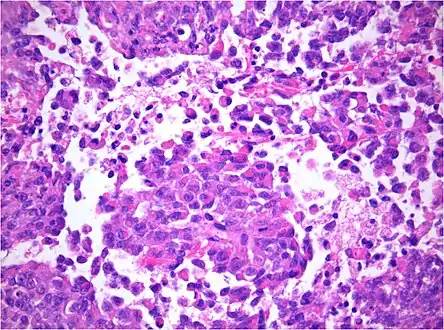

AT/RT and rhabdoid tumor share the term "rhabdoid" because under a microscope, both tumors resemble rhabdomyosarcoma.

AT/RT Histology with numerous rhabdoid tumor cells

Rhabdoid Tumor Cell - 400X Magnification

The tumor histopathology is jumbled small and large cells. The tissue of this tumor contains many different types of cells including the rhabdoid cells, large spindled cells, epithelial and mesenchymal cells, and areas resembling primitive neuroectodermal tumor (PNET). As much as 70% of the tumor may be made up of PNET-like cells. Ultrastructure characteristic whorls of intermediate filaments are seen in the rhabdoid tumors (as with rhabdoid tumors in any area of the body). Ho and associates found sickle-shaped embracing cells, previously unreported, in all of 11 cases of AT/RT.[18]